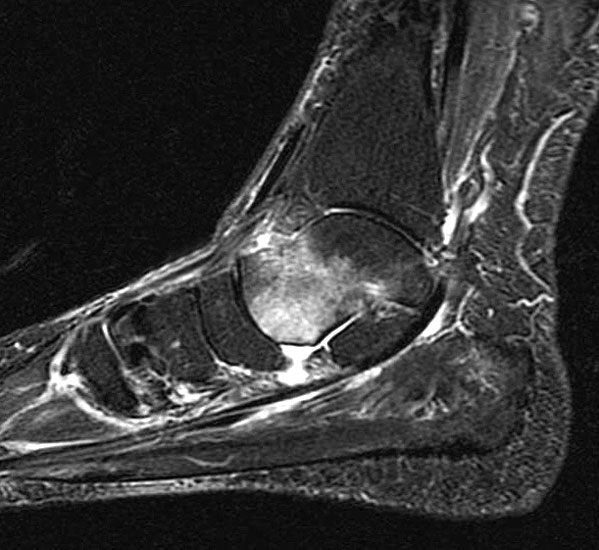

Abbildung 7

• Talusnekrose (Ödem in umschriebener Region des Talus, ev. Demarkation (Abb. 7), subakuter Beginn, Ruhe- und Belastungsschmerz)